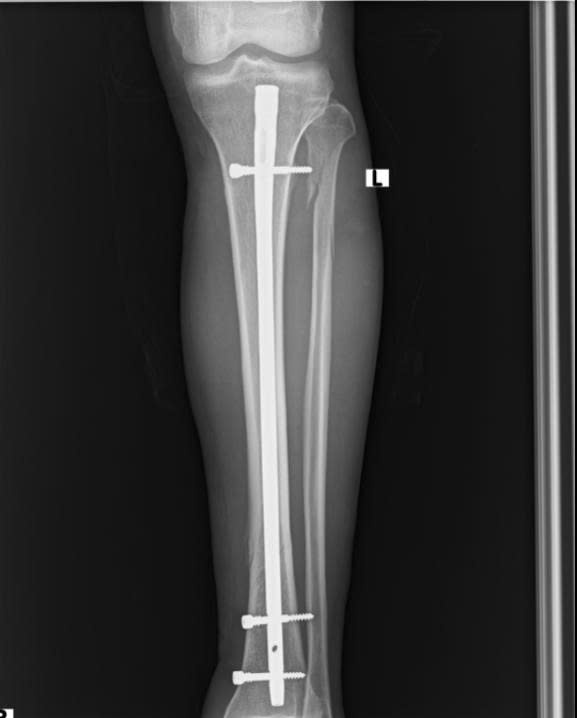

Hình ảnh: Xquang xương sau phẫu thuật

Đáp ứng yêu cầu điều trị hiện đại, Bệnh viện Đa khoa Hòa Bình đã ứng dụng thành công kỹ thuật đóng đinh nội tủy có chốt ngang dưới màn hình tăng sáng (C-arm) – một phương pháp ít xâm lấn, an toàn và hiệu quả cao trong điều trị gãy xương ống dài. Chỉ với một đường rạch da nhỏ khoảng 3–4cm, đinh nội tủy được đưa vào ống tủy qua hệ thống định vị dưới C-arm, cố định bằng chốt ngang hai đầu mà không cần mở ổ gãy. Kỹ thuật này giúp:

- Hình ảnh X-quang sau mổ cho thấy xương được nắn chỉnh và cố định vững chắc

- Sau 3 tháng, mức độ can xương vượt trội, tương đương mổ mở sau 6 tháng – chứng minh hiệu quả vượt trội của kỹ thuật